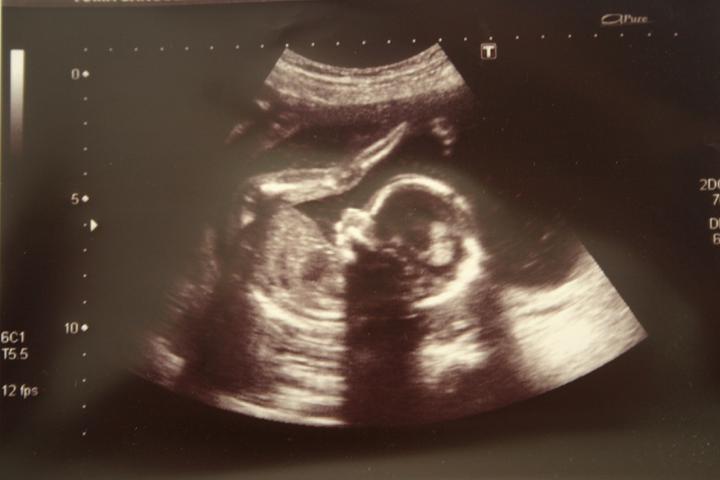

Dneska nástup na mateřskou a 42dní do termínu porodu. :o)

66 dní do porodu?? No potěš! :oD

Tak to je vtipný - koník mi píše 100dní do porodu - já se ještě ani pořádně nerozkoukala! S Vítkem to tak neutíkalo. Ale už se všichni moooc těšíme!